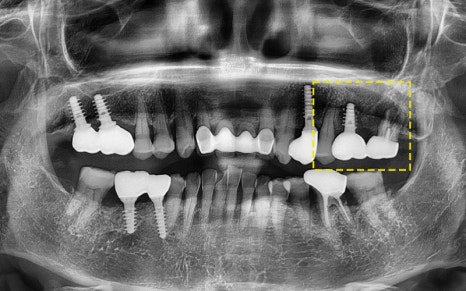

The photos above show the implant that was actually removed.

The screw body had snapped due to metal fatigue,

and around the head there was a large amount of tartar and inflammation.

The surrounding gum bone had melted away,

which eventually led to extraction of the adjacent tooth as well.

In the end, the implant had to be placed again,

and overall reconstruction was needed.

2025.06.18

After carefully considering the oral condition,

we placed the implant in the proper position and direction!